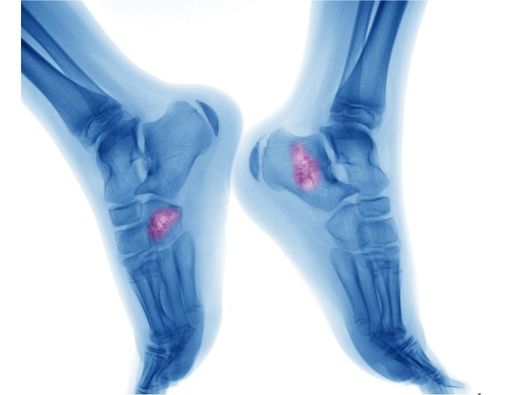

Pasien kanker tulang osteosarkoma yang tengah menjalani terapi pengobatan cenderung tidak memiliki nafsu makan.